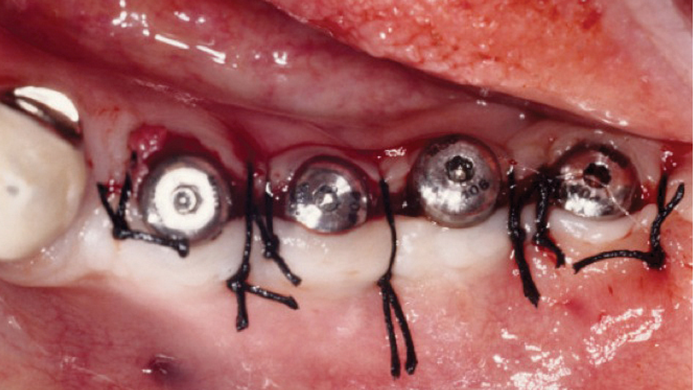

Clinical case: Ridge splitting technique using SmarThor + AnyRidge as expander

- Courtesy of Dr.Kwang-Bum Park, Korea -

AnyRidge, ridge splitting, GBR, Dr. Kwang-Bum Park, mandibular posterior, SmartThor, Mega-Oss, thin ridge, bone regeneration

AnyRidge implant system. SmarThor, Mega-Oss